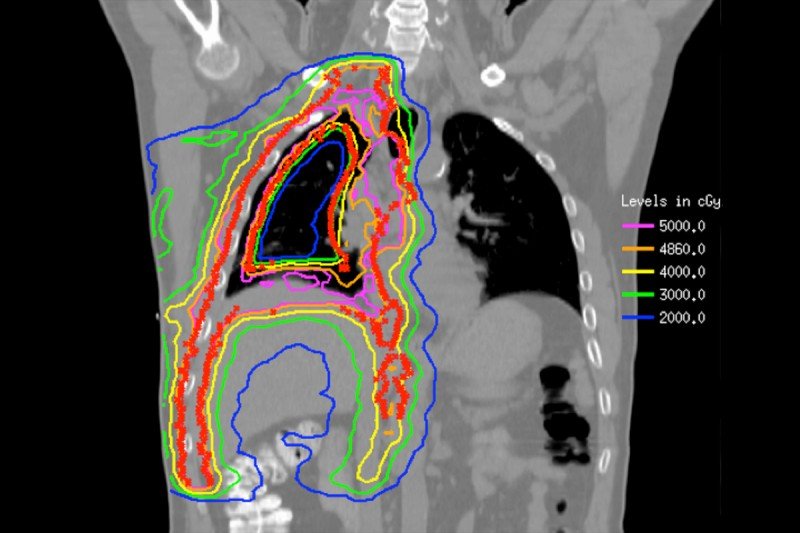

Malignant Mesothelioma Cancer | Symptoms and Treatment Guide from takebuz.com Therefore, researchers have started to explore different multimodality treatment approaches, in which often combinations of surgery, chemotherapy, immunotherapy, and rt are investigated. What are the treatment options for pleural mesothelioma? Learn how treatment can improve the prognosis of pleural mesothelioma Request a free informational guide for immediate overnight delivery. Free case evaluation · financial assistance · treatment options Jul 26, 2021 · pleural mesothelioma is typically treated with a multimodal approach, combining standard treatments like surgery, chemotherapy and radiation. Hindawi's academic journals cover a wide range of disciplines. Learn how treatment can improve the prognosis of pleural mesothelioma

Free health solutions · contact us now · help filing a claim Free case evaluation · financial assistance · treatment options However, study authors note that the procedure should only be adopted in centers with substantial surgical experience. Therefore, researchers have started to explore different multimodality treatment approaches, in which often combinations of surgery, chemotherapy, immunotherapy, and rt are investigated. Request a free informational guide for immediate overnight delivery. A pleural mesothelioma treatment plan will largely depend on the cell type and stage of disease. Jul 26, 2021 · pleural mesothelioma is typically treated with a multimodal approach, combining standard treatments like surgery, chemotherapy and radiation. 1 day ago · surgery for malignant pleural mesothelioma after radiotherapy may increase overall survival rates, according to a study. Learn how treatment can improve the prognosis of pleural mesothelioma The guide includes an overview of financial compensation help, top treatments, and more. Generally, treatment plans are not intended to cure the disease. The guide includes an overview of financial compensation help, top treatments, and more. Ask a question, get an answer asap®